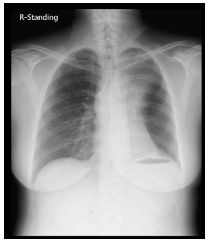

7.CC: cough for one year and back pain